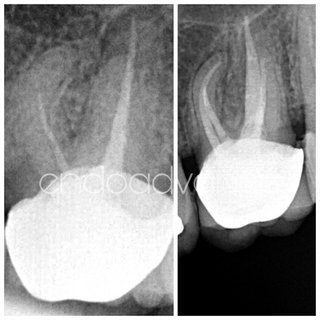

Αρχική ενδοδοντική θεραπεία σε άνω γομφίο με περίπλοκη ανατομία